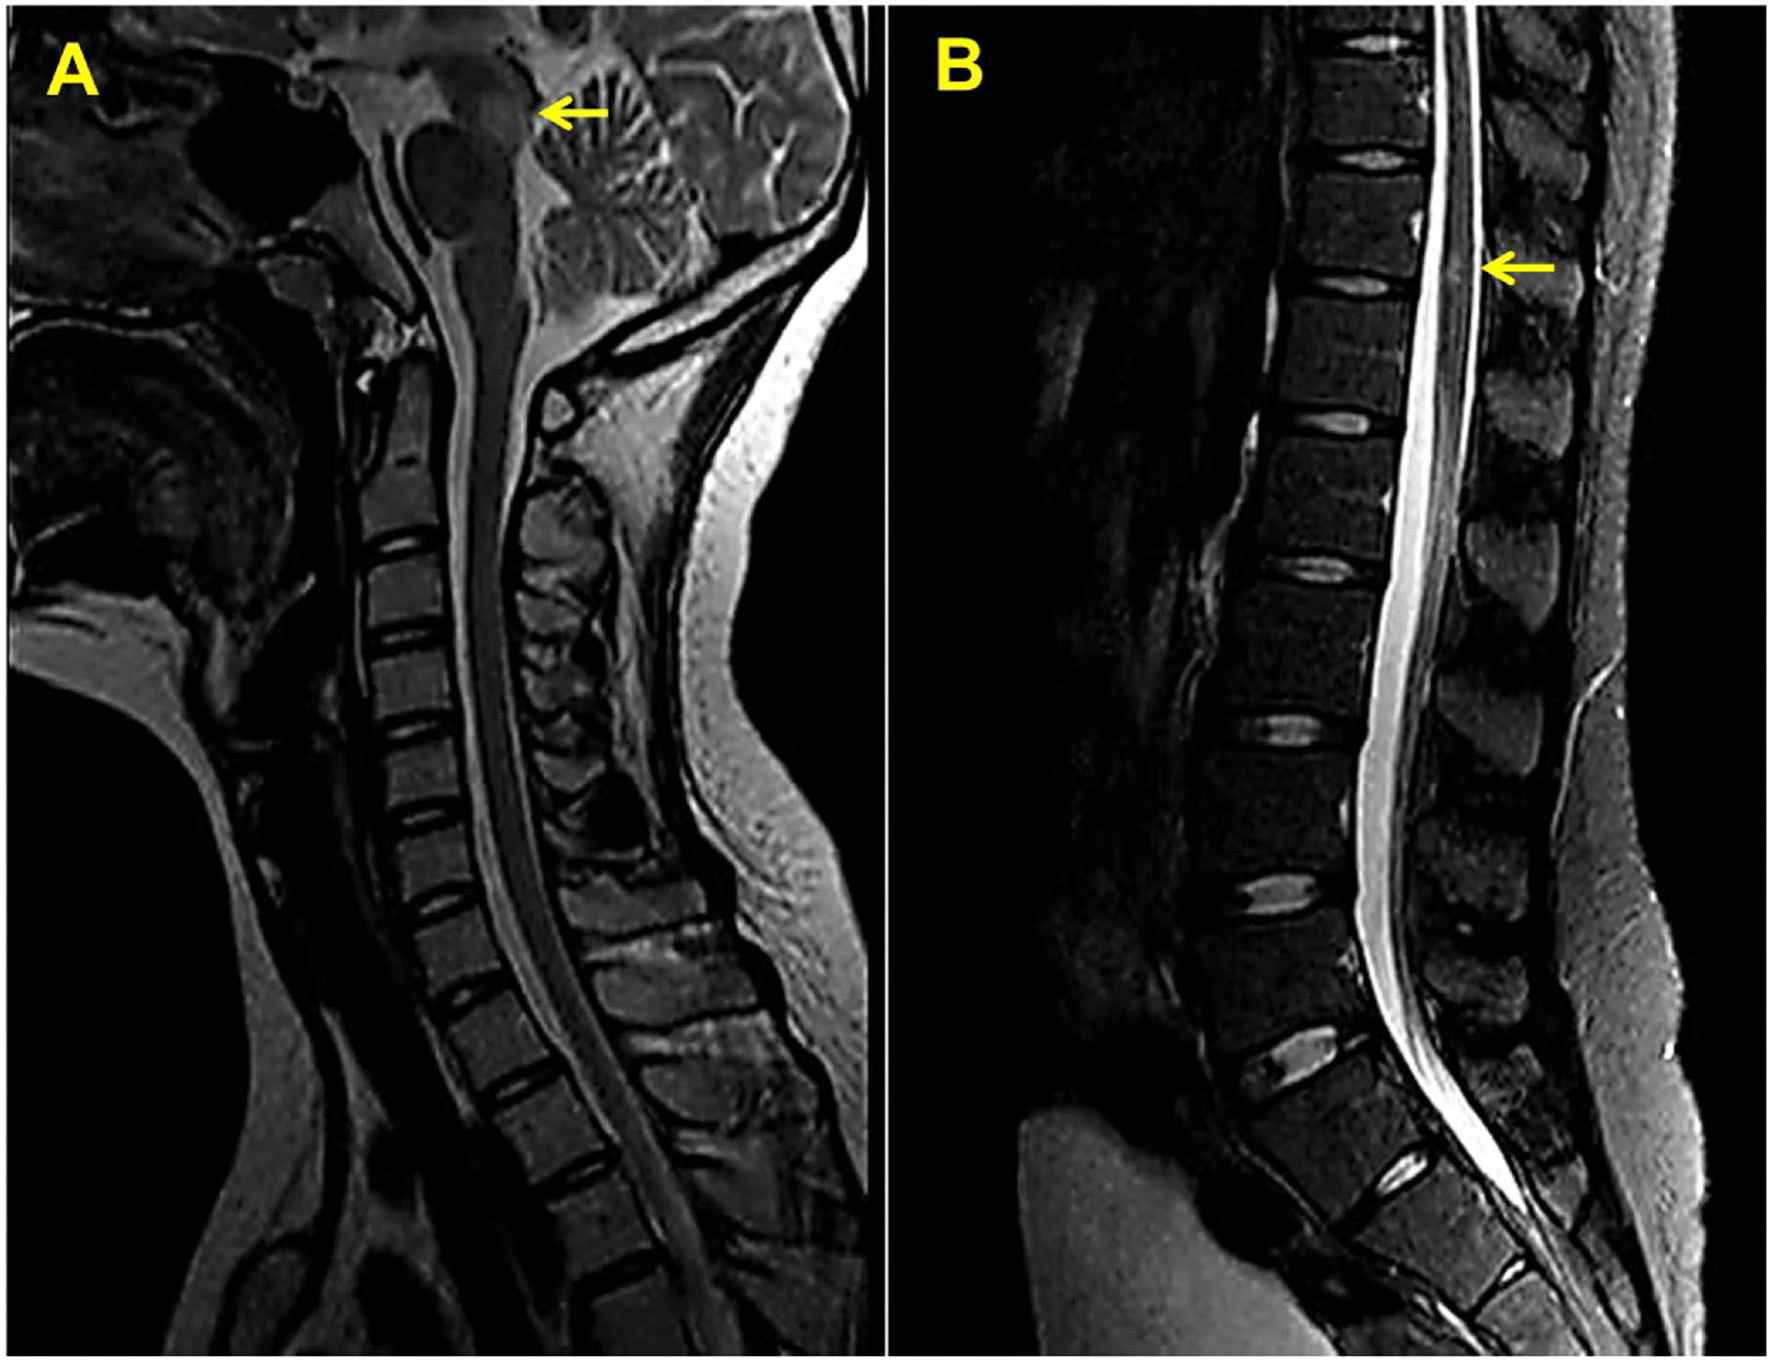

A 14-year-old girl presented with diplopia, left eyelid ptosis, right facial numbness, and right lower limb weakness since 1 month prior, which had progressively worsened. Physical examination revealed an impaired vision of both eyes, diplopia, left eyelid ptosis, right facial paresthesia, and hyperreflexia of both sides. There were no meningeal signs and no cervical, axillary, or inguinal lymphadenopathy. Routine blood tests, including blood cell counts, albumin level, transaminases, and C-reactive protein, were not significant. Brain MRI revealed multiple coin-like white matter lesions and one mesencephalon lesion (Figure 1A). Sagittal T2-weighted imaging of the brainstem and the spinal cord showed an enhanced lesion in the cerebral peduncle (Figure 2A) and in the spinal cord at the level of thoracic 12 (Figure 2B). Cerebral spinal fluid analysis showed leukocytes within the normal range, glucose was 6.25 mmol/L, albumin was 0.128 g/L, total Ig was 0.0563 g/L, IgG synthesis rate was 0 mg/day, and there were no detectable oligoclonal bands. The visual evoked potential (VEP) test was normal. She had a history of bilateral lacrimal gland enlargement about 6 months before, and a surgery was performed to correct this. Histological examination indicated lymphoproliferative changes, and the number of IgG4+ cells was over 220/HPF. Serum IgG4 was elevated (3.45 g/L, normal range 0.049–1.35 g/L). The patient was diagnosed as “IgG4-RD” and received oral glucocorticoid combined with cyclosporin but stopped 3 months later. The patient's family history was not remarkable. Based on the symptoms and MRI findings, the patient was suspected of MS and was given prednisone and intravenous immunogloblin (IVIG). Her diplopia and ptosis improved significantly and was discharged. One month later, she was administered 1 g of methylprednisolone for 5 days, followed by 70 mg of prednisone daily since her abnormal gait and lower limb weakness persisted. The prednisone was tapered to stop while recombinant interferon (IFN) β-1b was given every 2 days subcutaneously for 6 months. She did not receive any treatment for over 1 year until the development of enlargement of lymph nodes in the submaxillary and inguinal areas. Fourteen milligrams of Teriflunomide was given daily; however, her symptoms persisted. Six months later, the patient came to our department with lymph node enlargement and right-side numbness and weakness, but she denied any fever, unintentional weight loss, fatigue, or change in appetite. Laboratory tests revealed normal counts of leukocytes and platelets, the hemoglobin level, the albumin level, the serum creatinine level, and C-reactive protein. Antinuclear antibodies, extractable nuclear antigen antibodies, anti-neutrophil cytoplasmic antibodies, and anti-phospholipid antibodies were all negative. Serum IgG was 70.7 g/L (normal range 8.0–15.5 g/L), IgG4 was 28.5 g/L, and IgE was 4,810 mg/L (normal range 5–150 mg/L), while IgA and IgM were within the normal range (Figure 3). Chest computerized tomography and abdominal ultrasonography were not significant. A biopsy of the left inguinal lymph node was performed. The histopathological evaluation of the biopsy specimen of the inguinal lymph node revealed mixed inflammation containing predominantly plasma cells (Figures 4A–C). No granuloma, prominent necrosis, “onion skin pattern” mantle zones, or “lollipop lesions” were found. Immunostaining showed an increased number of IgG4+ plasma cells (>200/HPF) and an elevated ratio of IgG4+ cells to CD138+ plasma cells (~80%) (Figures 4B,C). No mycobacteria, fungi, or parasites were noticed, and Epstein-Barr virus-encoded RNA 1/2 was negative. These findings were suggestive of an IgG4-RD involving the lacrimal glands, the brain parenchyma spinal cord, and the lymph nodes according to both the ACR/EULAR classification criteria (5) and the revised comprehensive criteria (6). She had a good response to oral prednisone 40 mg daily combined with mycophenolate mofetil 750 mg two times daily. In a consecutive 7-month follow-up, her lymphadenopathy and right-side numbness and weakness resolved. A repeated brain MRI revealed shrinkage of the intracranial lesions, and the lab tests showed a rapid drop in serum levels of IgG and IgG4 (Figures 1B, 3).

Figure 2. Sagittal T2-weighted magnetic resonance imaging of the upper (A) and lower (B) spinal cord. Yellow arrows indicate white matter lesions.

Neural symptoms and white matter plaques on MRI of this patient (Figure 1) usually prompt people to consider MS. MS attacks myelinated axons in the CNS, causing progressive neurological deterioration (11). This disorder usually presents in adults between the age of 20 and 45 years with female predominance (11). Its clinical symptoms are non-specific and usually include visual changes, numbness, weakness, and paralysis, depending on the amount and area of nerve damage. MS is usually diagnosed by demonstrating clinical and/or radiographic evidence of dissemination of disease in time and space (12). This disease is characterized by elliptical or ovoid lesions found in the white matter of the periventricular and juxtacortical regions, the cerebellar peduncles, the superficial pons, and the floor of the fourth ventricles (13). Spinal cord lesions are also commonly seen. T2-weighted imaging of the spinal cord demonstrates small and circumscribed high-signal lesions that are aligned with the long axis of the cord. The lesions are usually less than two vertebral segments in length and involve less than half the axial cord area (13). In this patient, MRI revealed multiple ovoid lesions in the white matter and mesencephalon, and an enhanced lesion in the spinal cord at the level of thoracic 12, which are similar to MS lesions. Because cerebral IgG4-RD and MS have distinct outcomes, distinguishing between these two entities is critical. However, clinical judgment is often required to make the classification given an absence of specific biomarkers and clear diagnostic criteria.